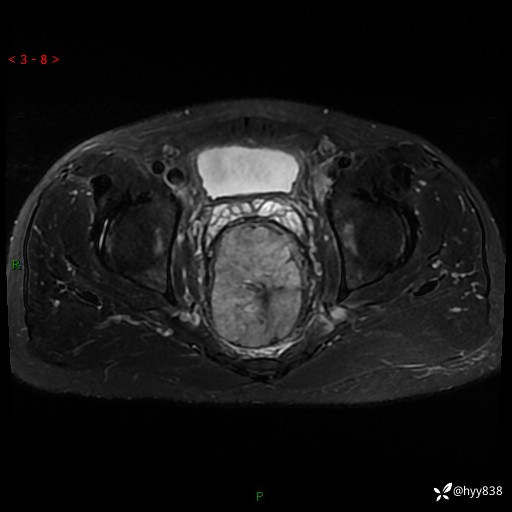

盆腔MRI平扫